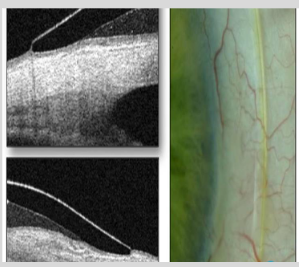

Describe the pic

Pt has PMD-kissing doves pattern

Difference map of the elevation of the eye presented in inferior pic measured in microns

Along the 1